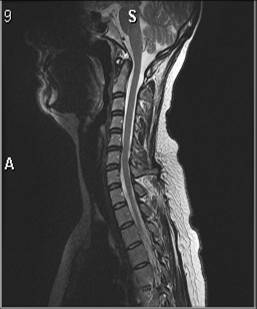

Columna cervicalis, normal, MR

MR af normal hals med to forskellige vægtninger så væsken i rygmarvshulen bliver henholdsvis sort (T1-vægtet) og hvid (T2-vægtet).

På dette billede er væsken i rygmarvshulen hvid (T2-vægtet).